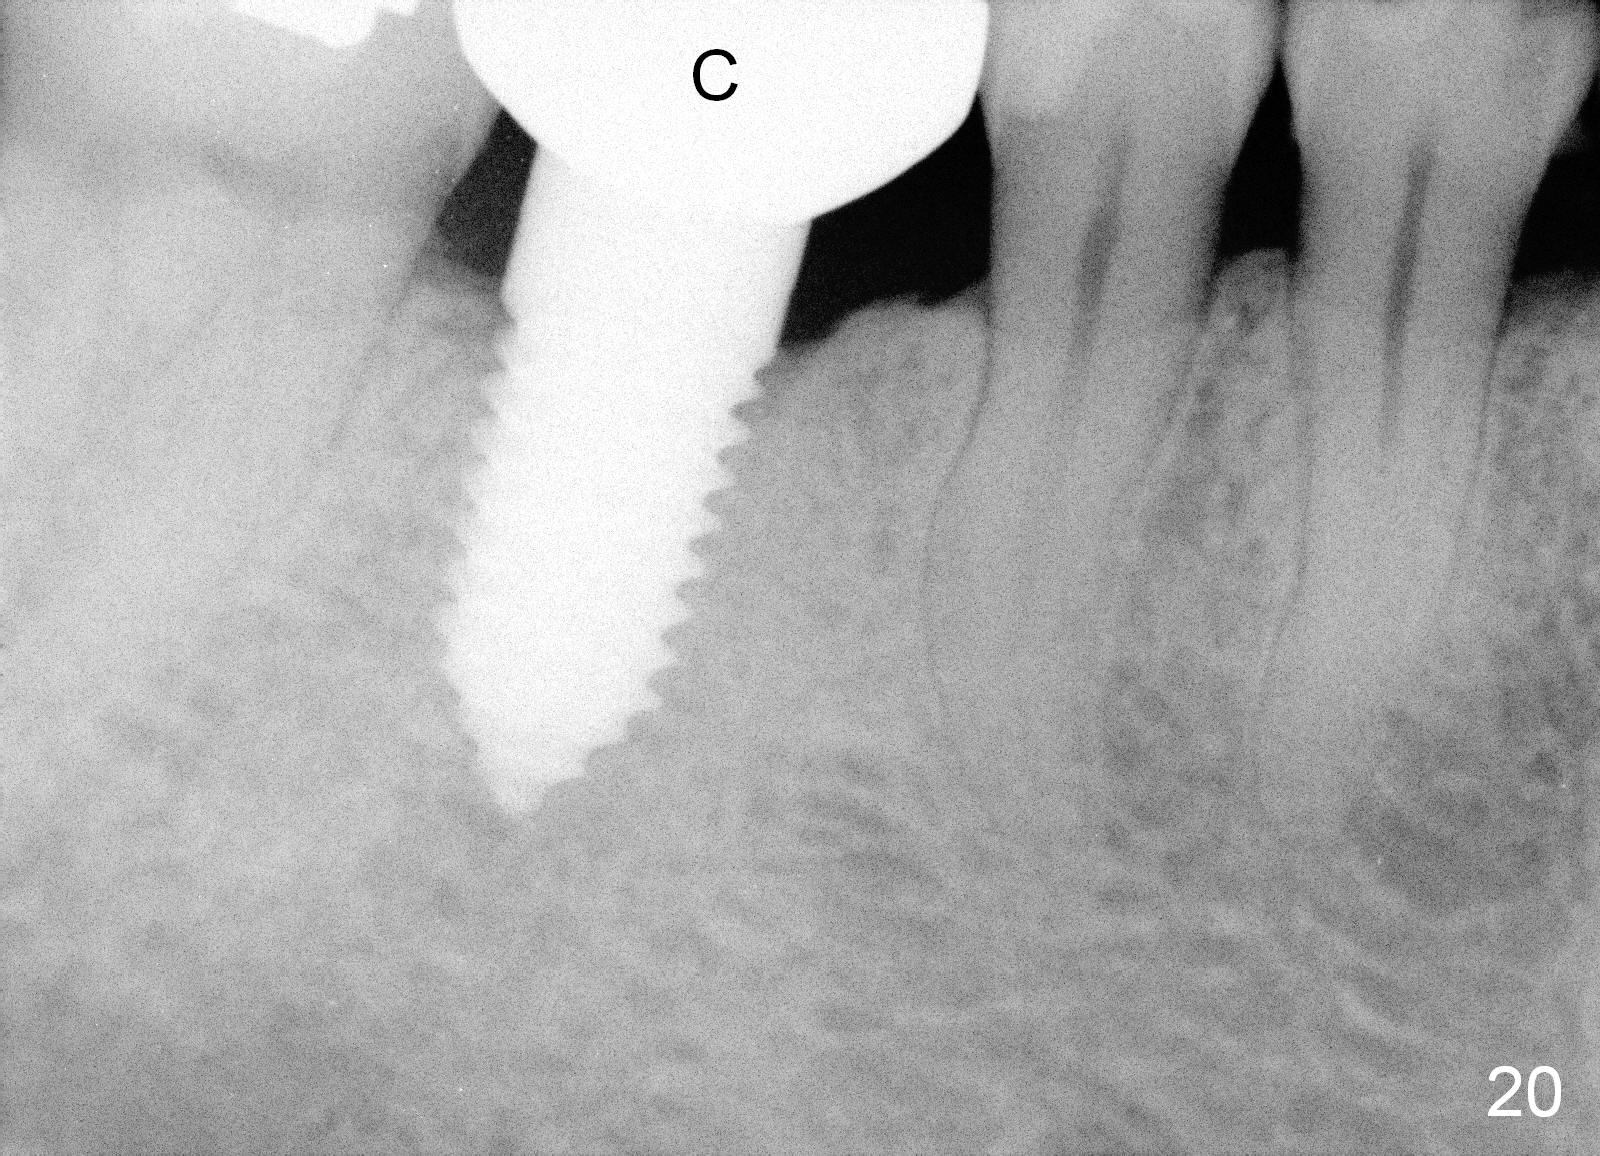

A 38-year-old lady agrees to have implant placement 7 years after loss of the crown of the lower right first molar (Fig.1,2). When the tooth is extracted, the septum is found to be low (Fig.3,4). To confirm it, a PA is taken (Fig.5). To initiate an osteotomy in the septum, it is trans-sectioned with thin osteotomes as shown in Fig.4 insert (black line). A 2 mm pilot drill is placed in the septum (Fig.6: P). The osteotomy is enlarged by 2.5-4.0 mm reamers (Fig.7,8), followed by insertion of 6x17 mm tapered tap at the depth 14 mm (Fig.9). The osteotomy is further enlarged by 4.5 and 5.0 mm reamers. A 6.0x14 mm one piece implant is placed initially. The trajectory is not ideal. A 6.0x14 mm one piece implant is placed initially. The trajectory is not ideal. The implant is removed from the osteotomy partially and reinserted with improved trajectory (Fig.11, compare to Fig.10 (red line)). Primary stability is high. There is not much bone mesiodistally so that the trajectory is easily changed in that direction. After abutment preparation, mixture of autogenous bone (harvested from reamers) and allograft is placed in the residual mesial and distal sockets (Fig.12). To contain the bone graft, an immediate provisional is placed (Fig.13 P). The occlusal plane of the provisional is significantly lower than that of the adjacent teeth to avoid micromovement of the implant. The patient is advised to eat soft food on the left side. Six days postop, the patient returns for prophy. The provisional is removed; the bone graft appears to be incorporating into the socket (Fig.14). After recementation, the provisional remains in place for 3.5 months; PA shows increased bone density in the mesial and distal sockets (Fig.15, compare to Fig.5,11). Due to insurance coverage, the patient defers fabrication of definitive restoration for at least 7 months. The immediate provisional is finally lost 8.5 months postop: the gingiva attaches to the 1-piece implant (Fig.16), while the density of the mesial socket increases (Fig.17 *) with formation of the cortex (lamina dura) coronally (v). Before the provisional (Fig.18 P) is removed for cementation of the definitive restoration, black shadow (*) is noted over the buccal gingiva. It is partially due to buccal placement (Fig.19) and partially due to buccal atrophy over a period of 10.5 months postop. How to prevent buccal placement? Positioning the first pilot drill in the septum buccolingually is a key. Eleven months post crown (Fig.20 C) cementation, the black shadow remains, but there is no tenderness. If the implant threads are immediately underneath the periosteum, there is tenderness.

CBCT taken 15 months post cementation shows that the implant is buccally placed (Fig.21 B), associated with possible postop buccal plate resorption (as compared to Fig.23 (coronal section of the site of #19). The buccal plate is not only thinner than the lingual one, but also concave (Fig.22 <). The tooth center (i.e., septum; Fig.23 T) is more buccally located than the center of the basal bone (B). Considering the denser bone lingually, the initial osteotomy should be more lingually (^). If the implant develops infection, it will be replaced by a more lingually placed implant (Fig.24 green).